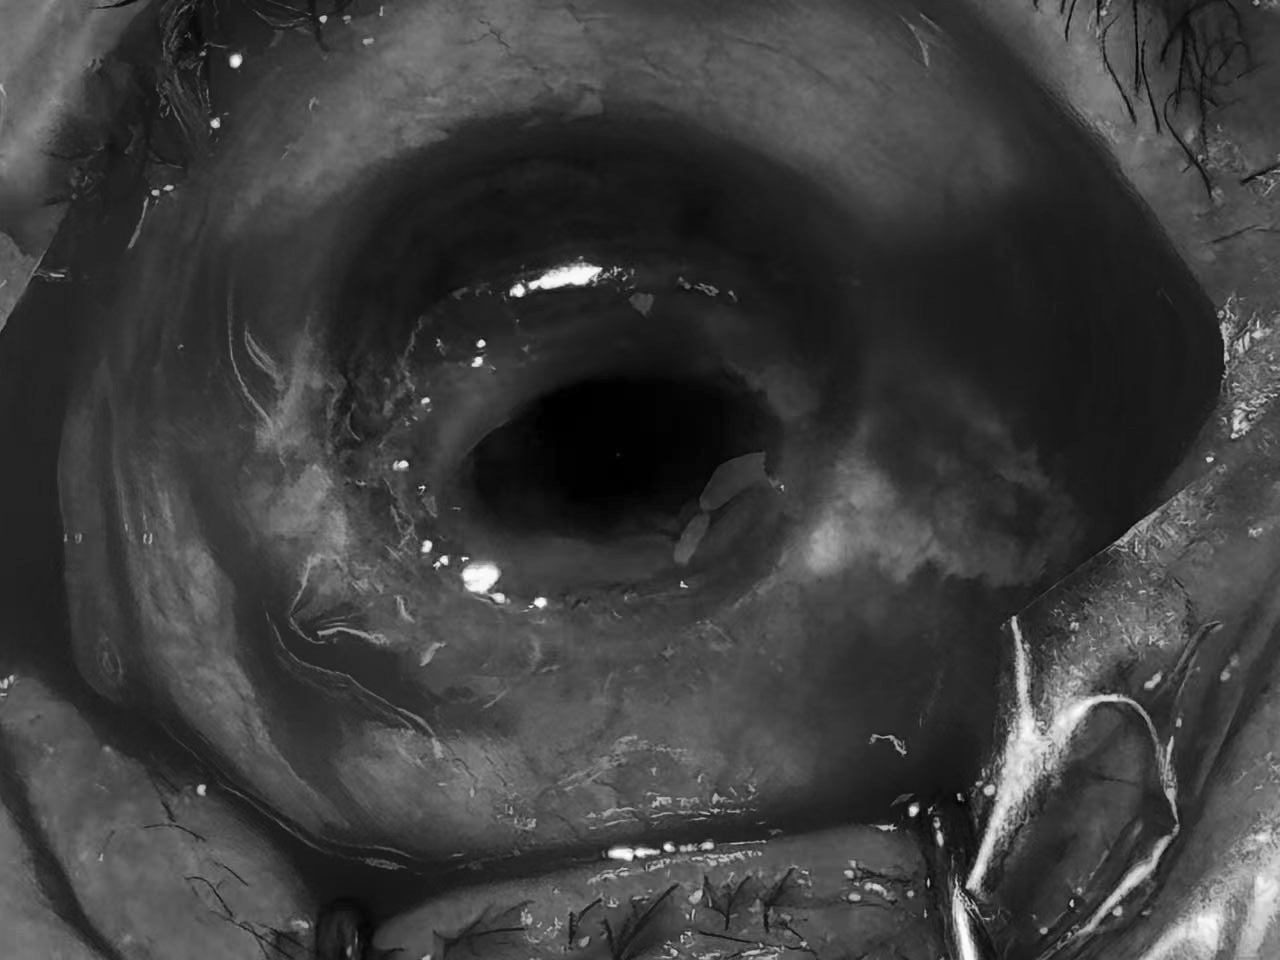

(图一:谢先生左眼角膜穿孔如图所示)

入院后,综合眼病科主任王莹及其眼科团队为谢先生展开全面检查,结果显示其左眼混合充血,结膜囊有少许分泌物,全角膜混浊且层次不清,下方存在 6.0mm×4.0mm 大小的穿孔,有 20.0mm×10.0mm×15.0mm 的暗红色眼内物膨出,同时伴随浅前房、房内大量血细胞及凝血块。考虑到眼球完整性已严重破坏,若不及时手术,不仅左眼可能完全丧失功能,还可能威胁右眼健康,王莹主任及其团队迅速制定手术方案,在表面麻醉 + 局部麻醉 + 神经阻滞麻醉下,为其实施 “左眼眼内容物剜出伴巩膜内填充” 手术。王莹主任带领团队凭借丰富经验和精湛技巧,妥善清除脱出组织、处理穿孔部位并进行巩膜内填充,手术顺利完成。术后经局部及全身抗炎、预防感染治疗,谢叔叔眼部疼痛明显缓解,病情逐渐稳定。